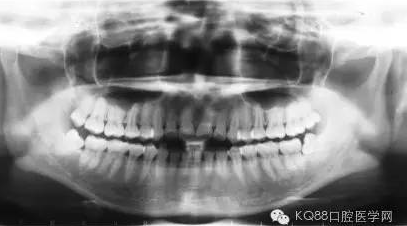

長時間的牙結(jié)石堆積最后會造成牙槽骨吸收和牙周袋形成,牙周袋內(nèi)很容易聚集食物殘渣和細菌。這樣惡化循環(huán),最后的結(jié)果是牙齒松動、脫落。

當牙齦下存在的牙結(jié)石,或有牙槽骨吸收跡象時,常規(guī)潔牙往往無法清除牙齦下的結(jié)石,此時需要進行牙周刮治了。

牙槽骨一旦吸收很難再生,所以,牙周刮治的目的是為了防止進一步的牙槽骨吸收,牙周袋形成以及牙齦出血。更有利于牙齒的穩(wěn)固和健康。

經(jīng)過牙周刮治(包括齦下刮治和跟面平整術(shù))的患者,每3到4個月需要進行一次牙周維護,因為他們牙齦下的堆積結(jié)石的幾率比一般人的要高。同時,掌握正確的刷牙方式(每天至少刷兩次),堅持使用牙線,對維護牙周健康也能起到一定的作用。

信息來源:KQ88口腔醫(yī)學網(wǎng)